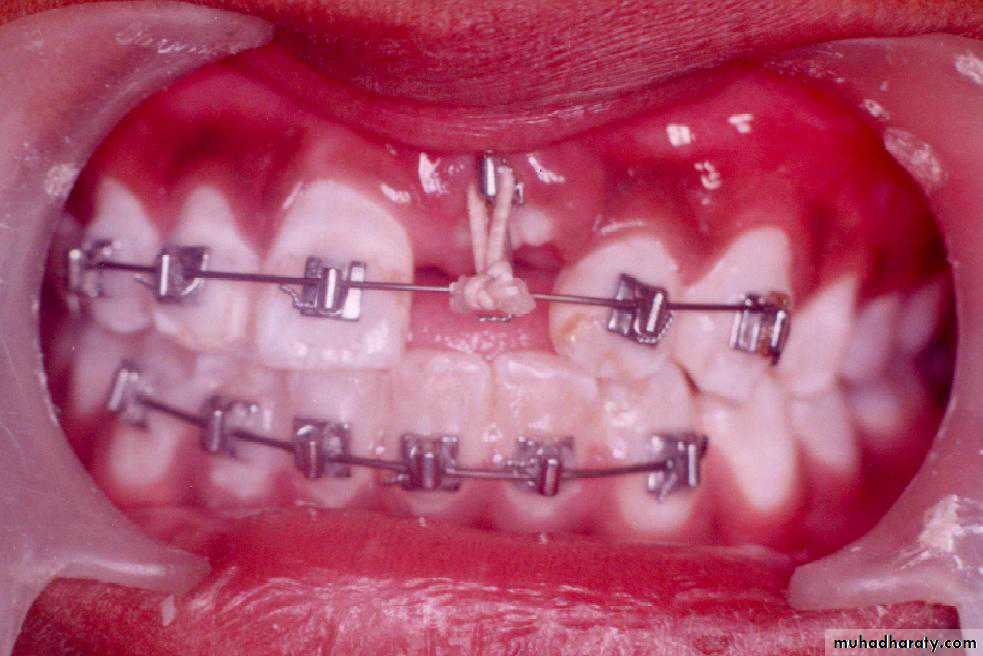

Surgical exposure :the path of eruption is not obstructed

Surgical exposure with orthodontic traction: the path of eruption is obstructed

Surgical exposure with orthodontic treatment (palatal approach )